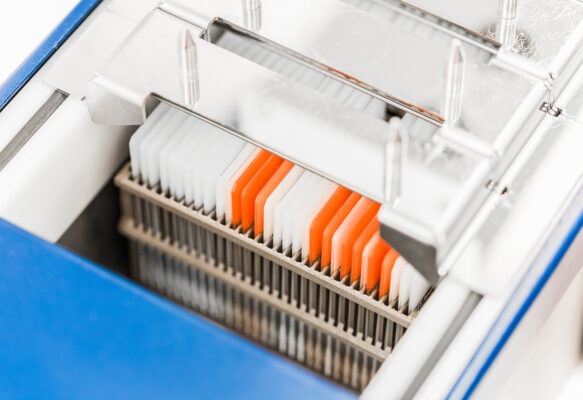

Cromatec – Linear Automatic Slide Stainer

Cromatec is a revolutionary slide Stainer from German engineers and histology equipment specialists SLEE Medical [...]